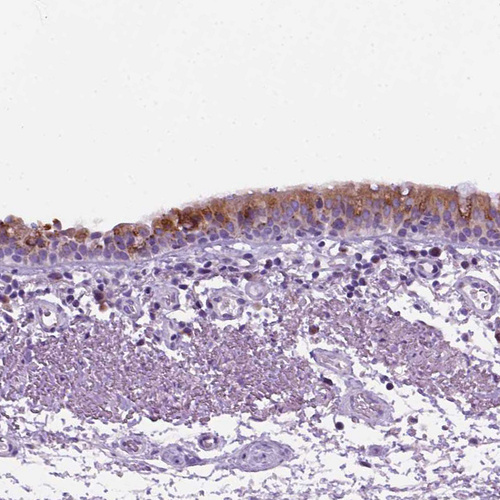

Immunohistochemical staining of human bronchus shows strong positivity in respiratory epithelial cells.